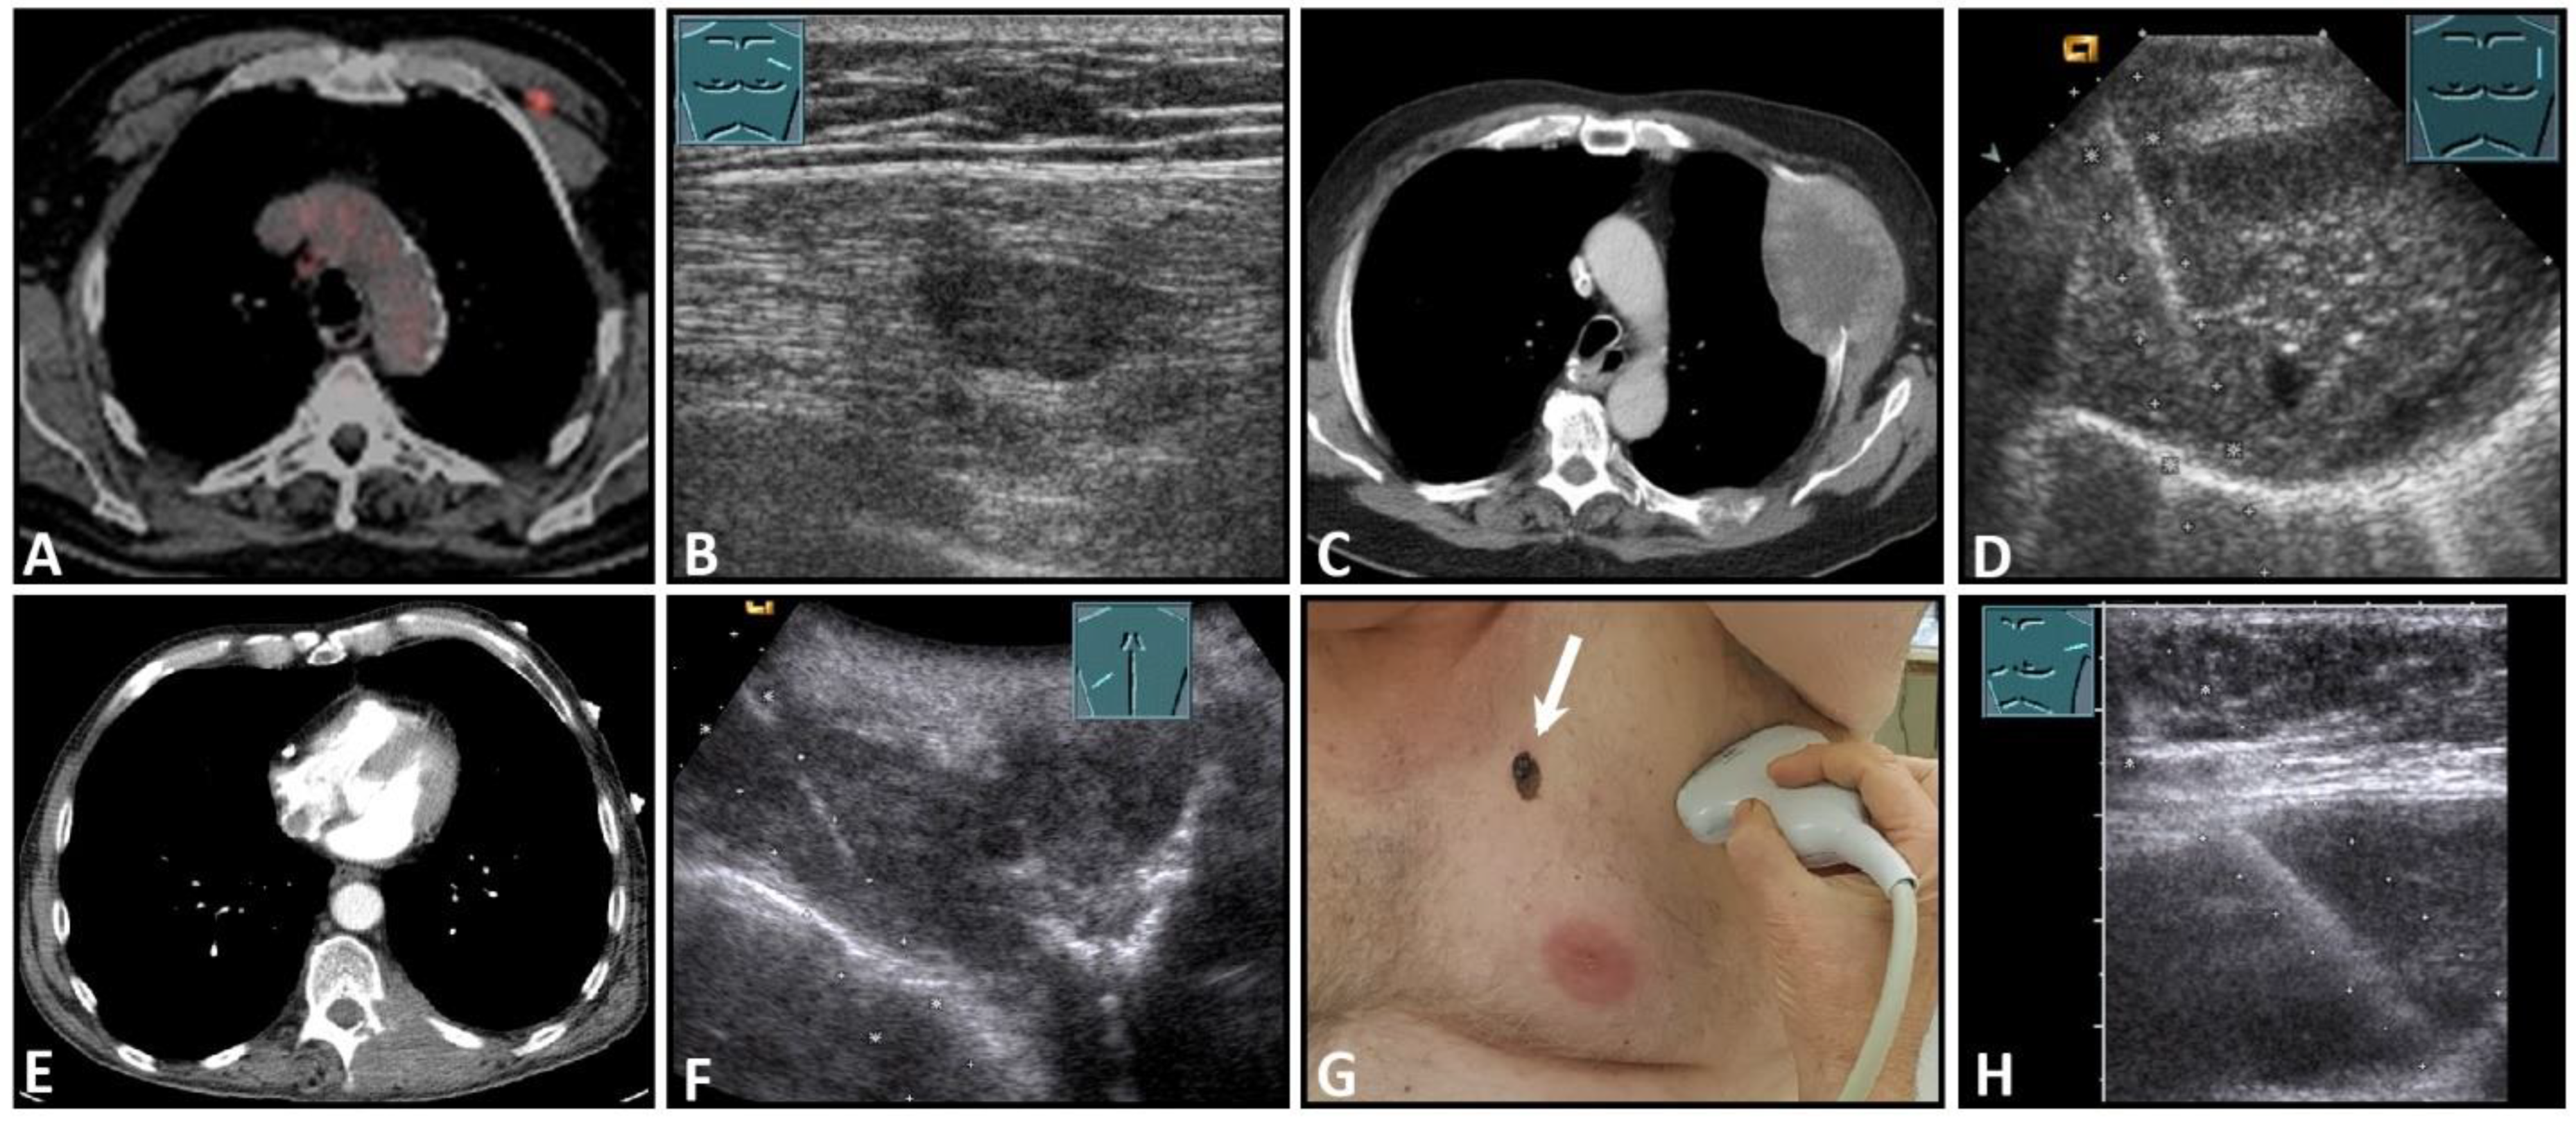

Figure 9.

Imaging of four patients with secondary malignant chest wall lesions. Positron emission tomography computed tomography (A) (provided by Prof. Dr. med. Markus Luster, Marburg, Germany) in a patient with small cell lung cancer and focal lesion on B-mode US in the chest wall (B). A patient with metastasis of an esophageal carcinoma: imaging on CT (provided by Prof. Dr. Andreas H. Mahnken, Marburg, Germany) (C) and B-Mode US with visualization of the needle reflex on US-guided biopsy (D). Paravertebral metastasis of vocal fold carcinoma with imaging on CT (E) and B-Mode US with visualization of the needle reflex on US-guided biopsy (F). Imaging of malignant melanoma in the pectoral skin region (arrow) (G) with regional lymph node histologically confirmed as melanoma metastasis (H).